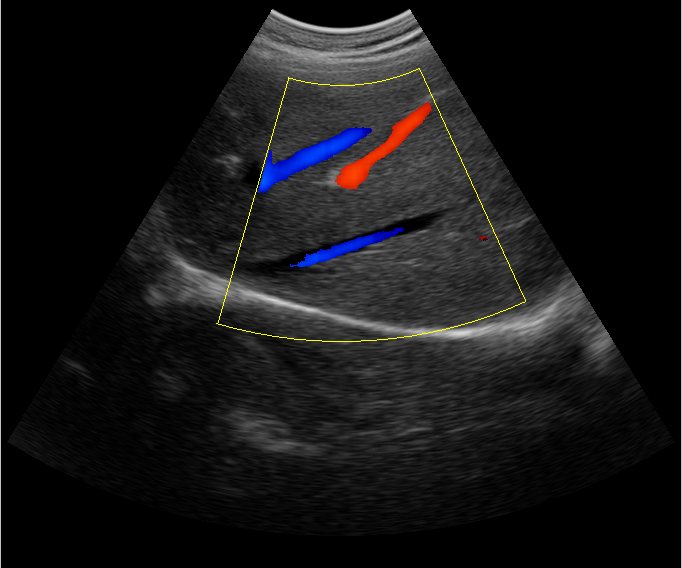

B超檢查主要是檢測(cè)肝臟的外形、大小、膽囊、門靜脈、回聲粗線等問題。由于乙肝病毒造成肝細(xì)胞破損嚴(yán)重,肝細(xì)胞出現(xiàn)問題,發(fā)生異常外形就會(huì)改變,通過B超檢查就能很清楚的檢查出肝臟受損的程度,以及肝臟的大小是否改變,肝臟是否發(fā)展為肝纖維化、肝硬化等。還可以檢查門靜脈主干內(nèi)徑是否增寬等情況。

肝臟B超還可以通過肝臟的門靜脈、回聲粗線、膽囊等指標(biāo)來診斷病情。由于肝炎病毒長(zhǎng)期侵害會(huì)造成肝細(xì)胞破損嚴(yán)重,肝細(xì)胞出現(xiàn)異常,肝臟發(fā)生異常時(shí)外形就會(huì)改變。通過肝臟B超檢查就能很清楚地看出肝臟的受損程度,以及肝臟的大小、形態(tài)、回聲等是否正常。有利于肝臟的疾病的正確診斷。